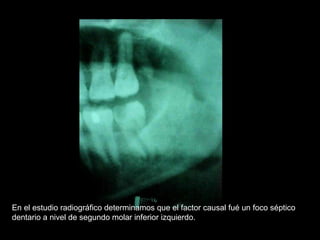

En el estudio radiográfico determinamos que el factor causal fué un foco séptico

dentario a nivel de segundo molar inferior izquierdo.